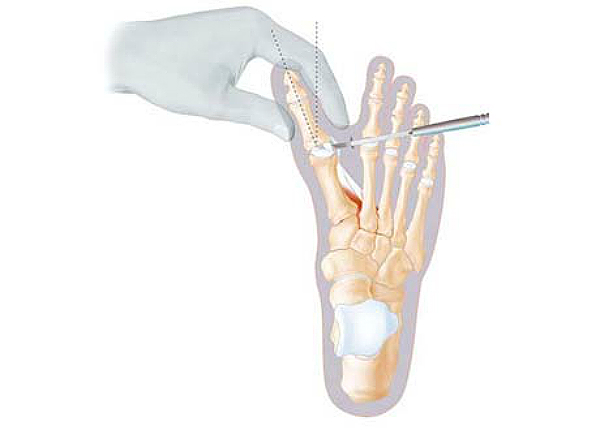

Медицинские решения: Операция по коррекции Hallux valgus